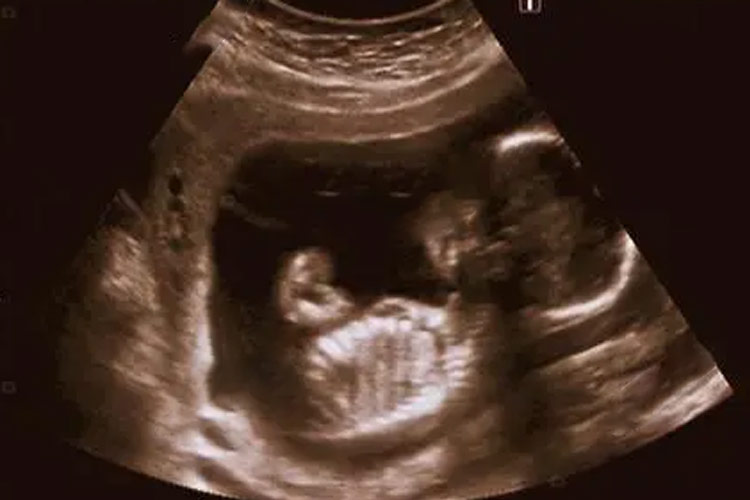

胎儿心脏彩超的推荐检查时间通常是在妊娠期的22-28周,但最佳时间通常是在怀孕24-26周,因为此时胎儿的心脏已经充分发育,可以通过超声波清晰地观察到心脏的结构和功能,从而更好地评估是否存在先天性心脏病或其他心脏异常。

1、22-28周:这个时间段内,胎儿的心脏已经发育得相对完善,大小适中,有利于医生进行细致的观察和检查,孕妇的羊水量也适中,胎儿在子宫内的活动空间较大,有利于胎儿体位的改变,从而更容易获得清晰的图像。

2、24-26周:在这个时间段内,胎儿的心脏结构已经发育得较为完善,医生可以更加准确地评估胎儿的心脏结构和功能。如果发现严重的致死性胎儿心脏病,医生可以及时建议终止妊娠进行引产手术,从而避免对孕妇和家庭的进一步伤害。

胎儿心脏超声检查不可过早也不可过晚,因为过早检查胎儿的心脏可能还未完全发育成熟,难以看出内部结构是否存在先天性心脏病的风险。过晚检查,虽然胎儿的心脏已经发育成型,但可能由于胎儿体积增大、羊水量减少以及胎儿骨骼声影等因素的干扰,使得心脏的某些结构难以看清。

胎儿心脏彩超作为孕期重要的筛查手段之一,其检查时间的选择至关重要。在妊娠期的22-28周,尤其是24-26周这一黄金时段,不仅确保了胎儿心脏发育的成熟度,也为医生提供了最佳的观察条件,能够更准确地评估胎儿心脏的健康状况。